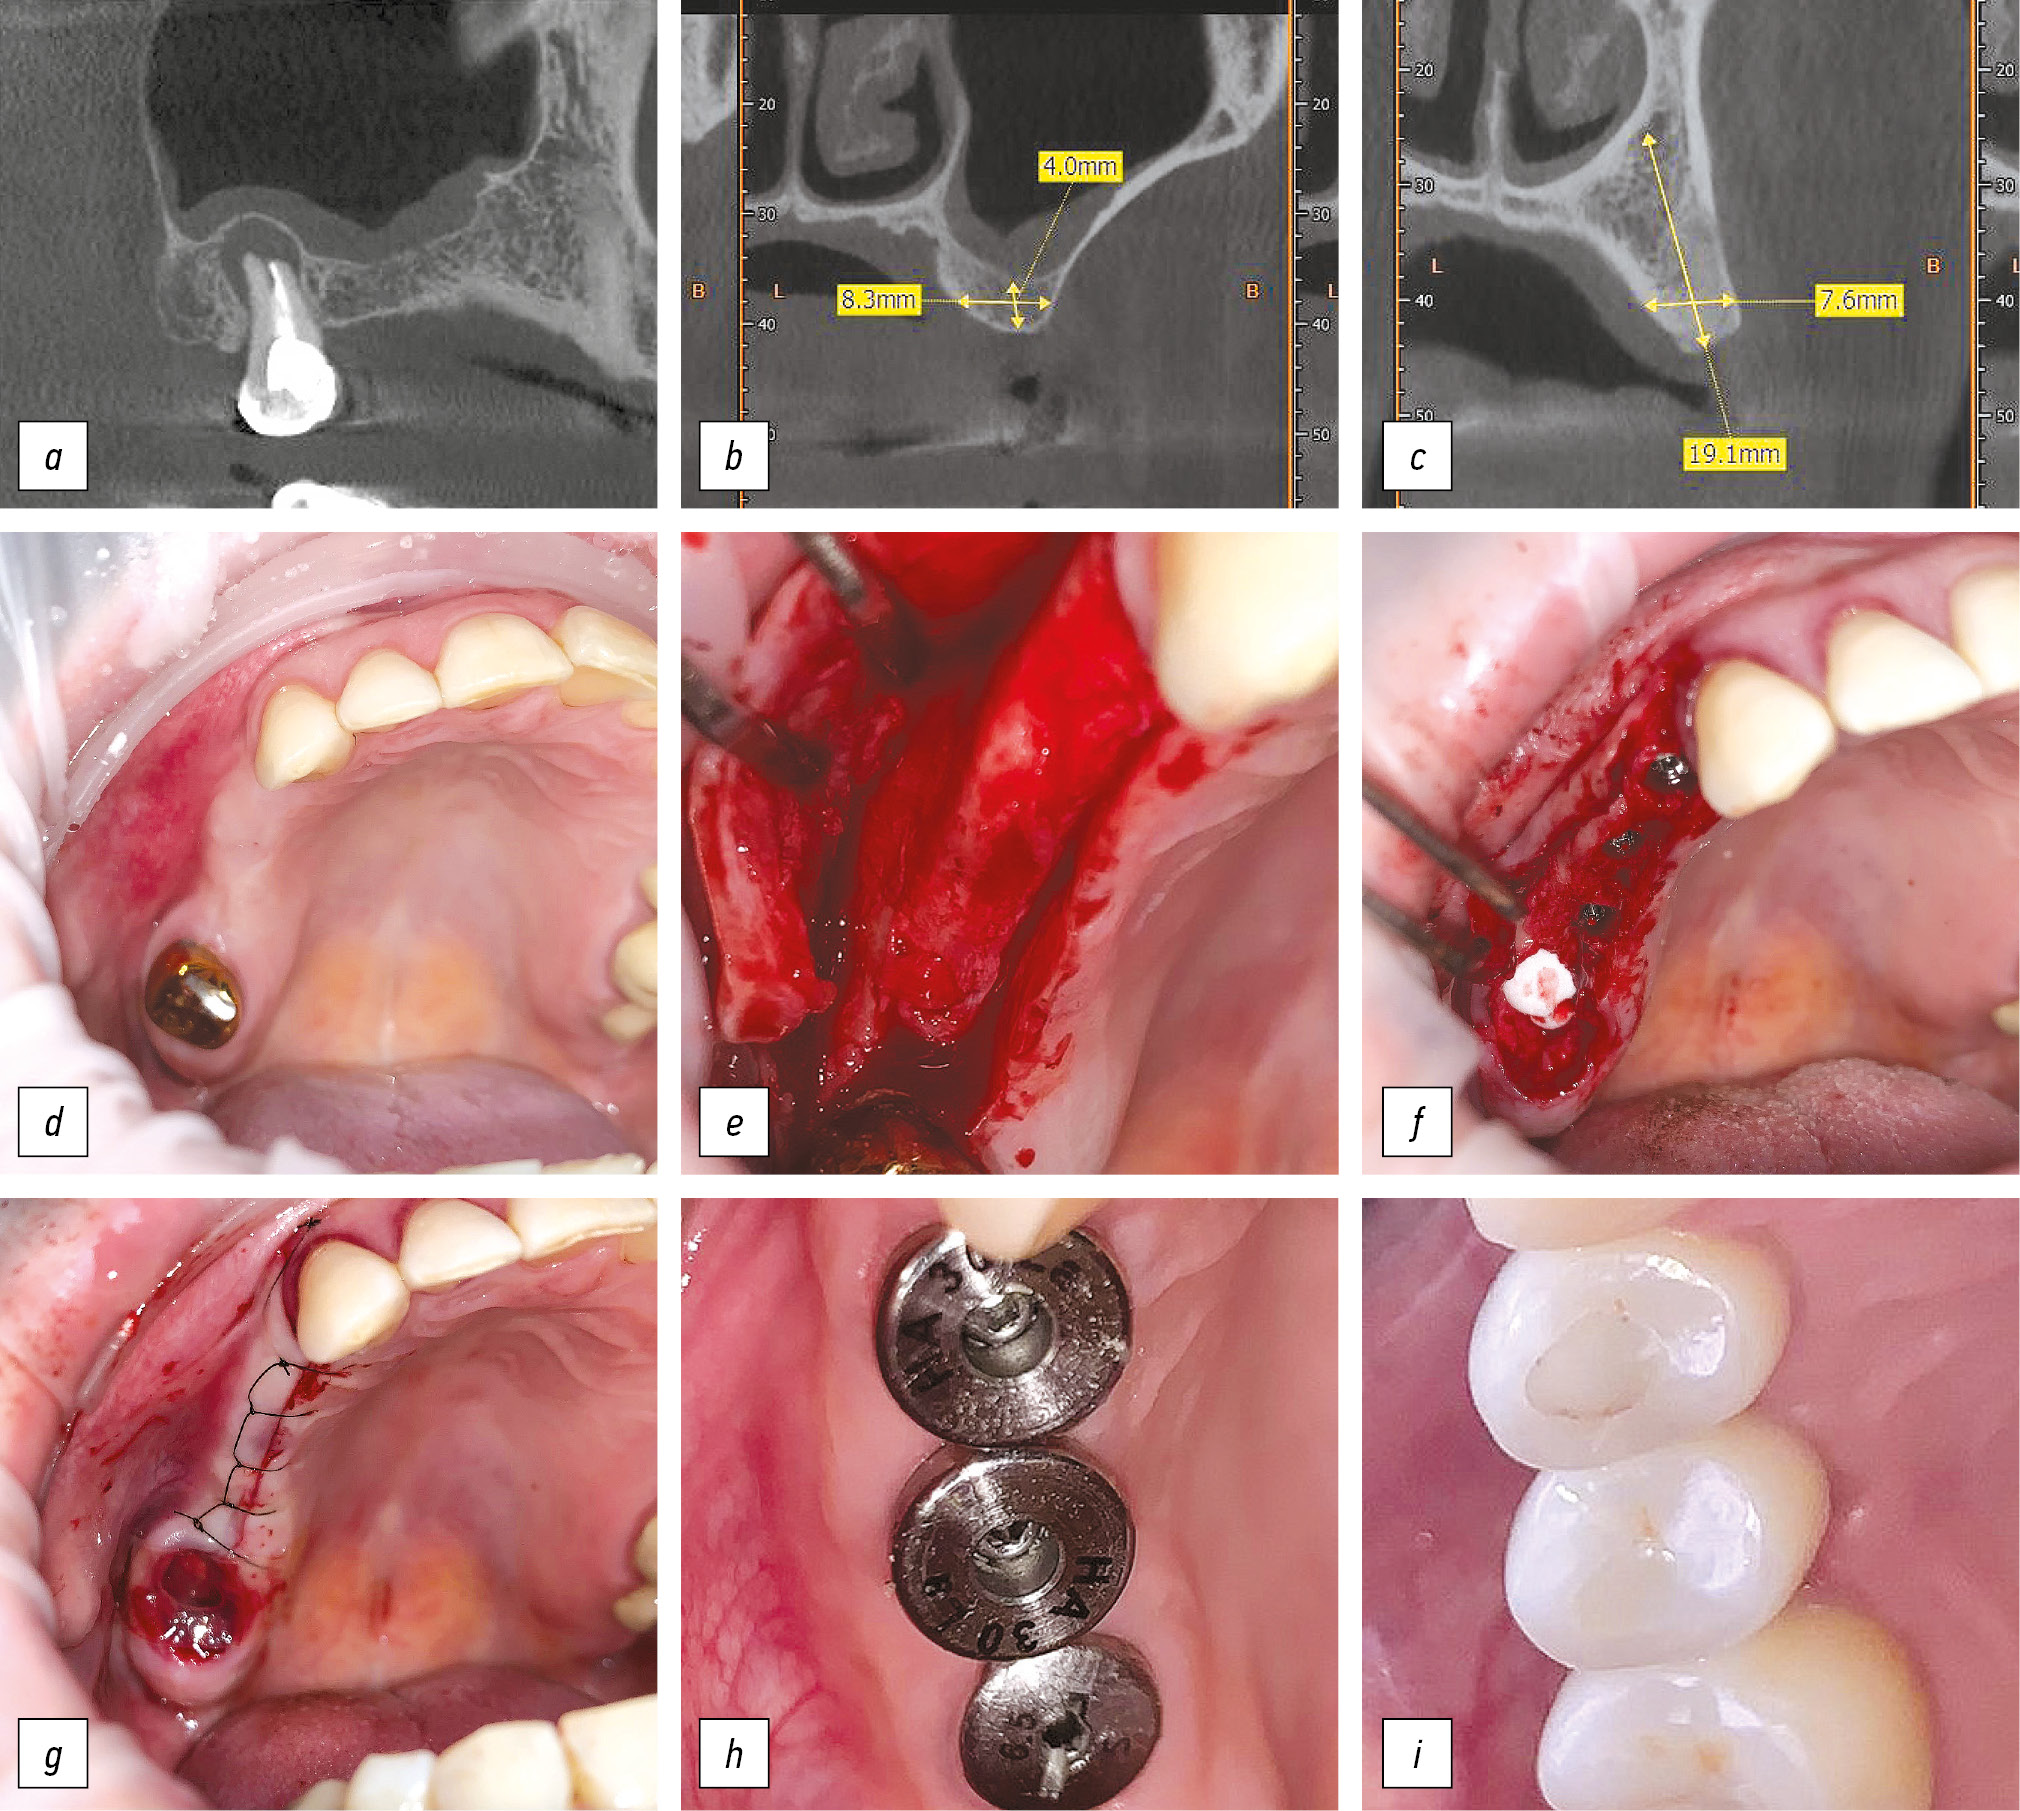

Рис. 1. Этапы стоматологической реабилитации пациентки Л., 37 лет: а, b, c — срезы компьютерной томограммы в области отсутствующих зубов; d — исходная клиническая картина в полости рта; e, f, g — этапы установки дентальных имплантатов в область отсутствующих зубов; h — установка формирователей десневой манжеты; i — фиксация окончательной ортопедической конструкции.

Fig. 1. Stages of dental rehabilitation of patient L., 37-years-old: a, b, c — sections of a computed tomogram in the area of missing teeth; d — the initial clinical picture in the oral cavity; e, f, g — the stages of installing dental implants in the area of missing teeth; h — installation of gingival cuff shapers; i — fixing the final orthopedic restoration.

Пациентка Л., 37 лет, обратилась с жалобами на частичное отсутствие зубов на верхней челюсти справа (рис. 1). При осмотре: включённый дефект зубного ряда верхней челюсти — отсутствие зубов 1.4–1.6, хронический гранулематозный периодонтит зуба 1.7. В соответствии с планом ортопедического лечения выполнено удаление зуба 1.7, установка дентальных имплантатов Synthes Pro в позиции зубов 1.4, 1.5 и 1.6 по двухэтапному протоколу с субантральной аугментацией закрытым методом в позиции имплантата 1.6. Заживление послеоперационной раны без признаков воспаления, швы сняты на 7-е сутки. Через 3 мес после установки дентальных имплантатов выполнена контрольная ортопантомограмма, где визуализируются признаки остеоинтеграции имплантатов, в связи с чем вторым этапом выполнена установка формирователей десневой манжеты (рис. 2).